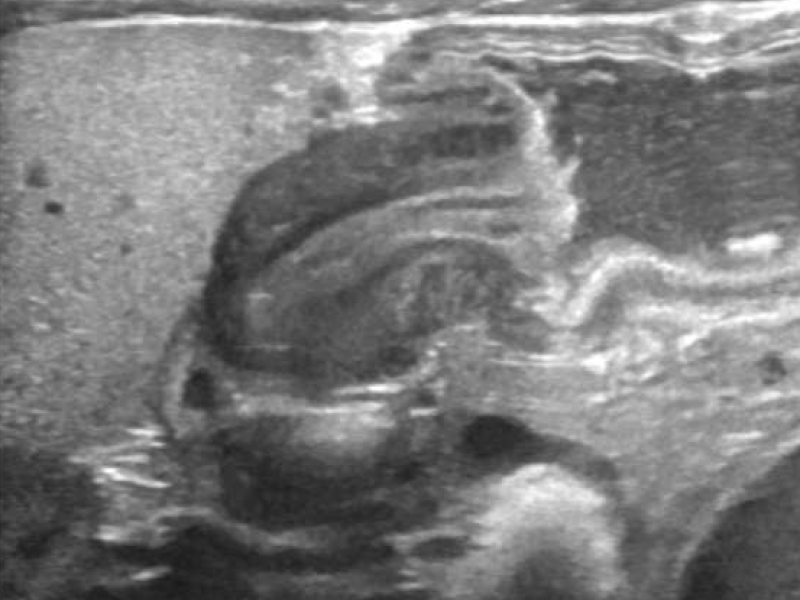

Imaging Case: Six Week-Old Infant with Projectile Vomiting

Case: A six week-old previously healthy, term infant via